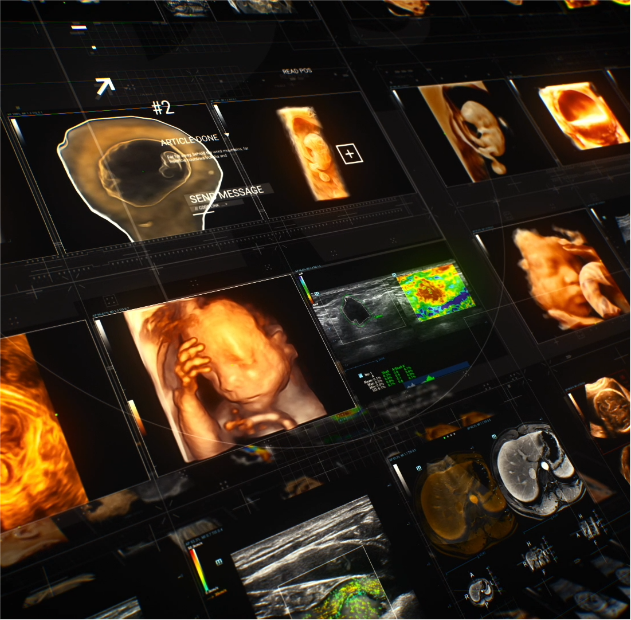

OptimizaciĂłn del rendimiento clĂnico y los resultados de los pacientes

Ayudando a los hospitales a crear beneficios de gran escala